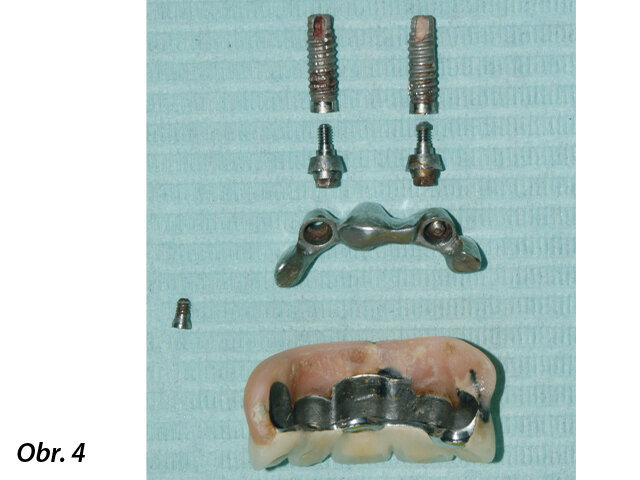

Vzhledem k nedostatečné oseointegraci bylo odstranění implantátů poměrně snadné (obr. 4). K odstranění byl použit nástroj pro odstraňování implantátů. Poté byla ihned umístěna provizorní snímatelná pryskyřičná náhrada s patrovou deskou. Z důvodu eliminace zánětlivých reziduí bylo kontraindikováno šití oblastí, do nichž budou zaváděny implantáty.

Konstrukce byla odšroubována, abutmenty odstraněny a implantáty snadno vyjmuty.